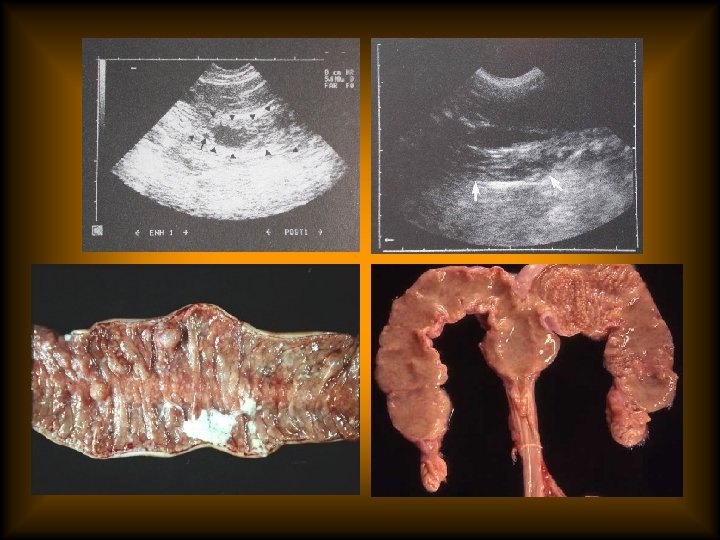

estrus過長 • 診斷 – 陰道抹片以角化的上皮細胞為主(90%)。 – monitoring serum progesterone (< 2 ng/ml) – ultrasonography

estrus過長 • 診斷 – 陰道抹片以角化的上皮細胞為主(90%)。 – monitoring serum progesterone (< 2 ng/ml) – ultrasonography – exploratory laparotomy

estrus過長 • 治療 – ovariohysterectomy – injection of Gn. RH or h. CG(50 -100

estrus過長 • 治療 – ovariohysterectomy – injection of Gn. RH or h. CG(50 -100 IU), no breeding this time – progestin therapy(medroxyprogesterone acetate, 20 -25 mg,SC) Side effect: cystic glandular hyperplasia and pyometra